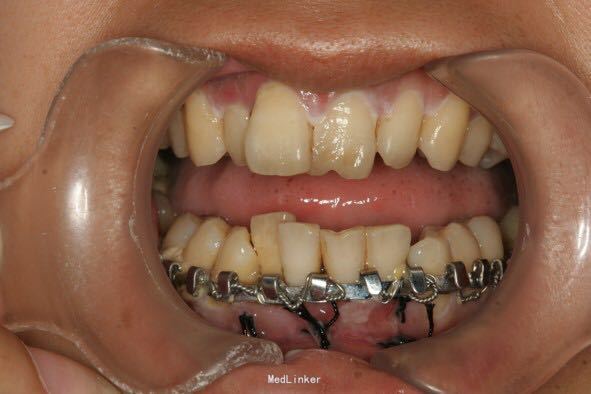

下颌前部可见唇与牙龈的撕裂、肿胀、牙松动,摇动损伤区的牙时,可见邻近数牙及骨折片随之移动,咬合错乱

下颌前部牙槽突骨折

处理:牙弓夹板固定骨折,缝合撕裂的牙龈

术后一个月拆除固定夹板,骨折愈合良好。